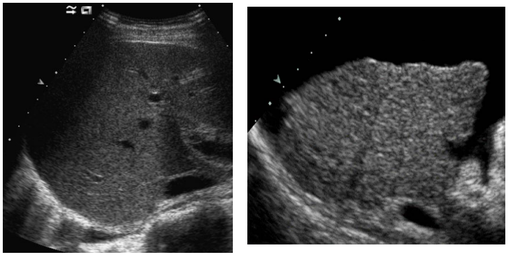

Foie : lésions focales

DANSE E. - UCL

Digestif MASTER 1 Foie